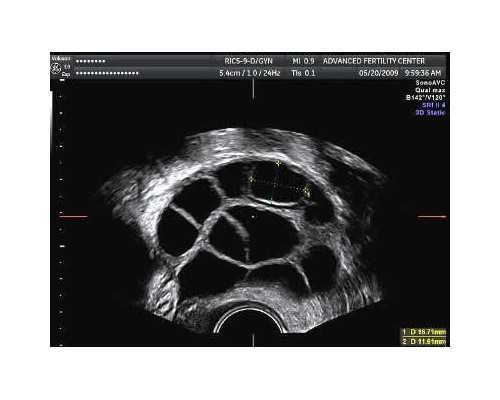

武汉协和医院目前能够开展第一代、第二代及第三代试管技术,拥有试管技术的医院一般都是可以做供卵的,不过是否有卵源就需要具体咨询了。

由于我国卫生部发布的人类辅助生殖技术明确规定,只有同时在做试管婴儿的女性,才允许额外捐卵,这就导致了卵源难等的情况。还有一点就是中国还属于比较传统的国家,捐卵很多人是无法接受的,导致武汉协和医院卵源短缺。所以想去武汉协和医院申请供卵只能先申请排队。

目前还不能单方面决定捐卵做试管婴儿。夫妻双方必须签署知情同意书,符合条件。但是武汉目前没有专门的卵子银行,经常需要排队等候。

年龄小于50岁或卵巢功能表明需要卵子捐赠的妇女;

女方经检查确实患有遗传病或者染色体异常的;

如果排除第一代和第二代试管婴儿患者反复着床失败的男性因素,那么也可以通过供体试管婴儿辅助怀孕。

捐卵前期需要准备好夫妻双方的身份证、结婚证、出生证,缺一不可,因为在我国,禁止单身人士进行试管婴儿或者捐卵试管。只有满足一系列条件,才能辅助人工受孕。而且卵子捐献者试管需要排队挂号,具体等待时间不确定。短的可能等几个月,长的可能等几年。